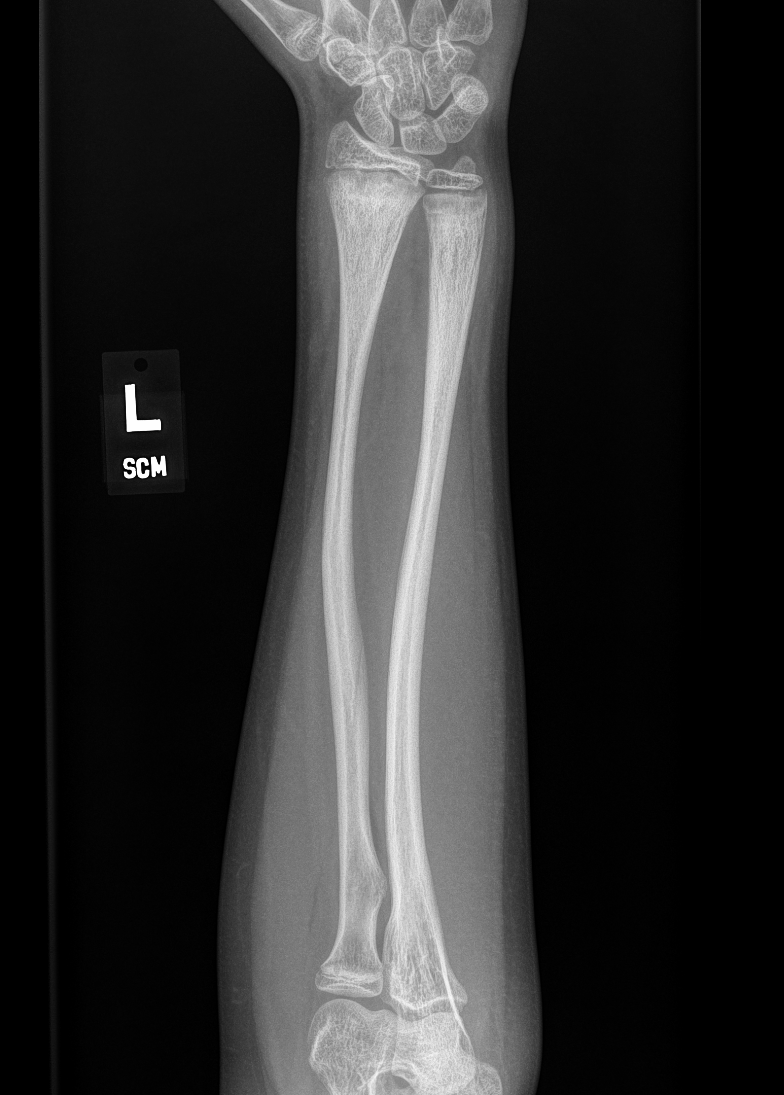

Info Images Findings Impression Reco/Acuity Case Images View Images / Launch Visage Case Notes History 2 month old suspected of being a victim of physical child abuse. No history of trauma, patient presents with subdural hematoma and rib fractures. Exam Skeletal survey Prior Study none Dicom View Reference Material

Section 1 Submit Findings CB1546 Findings Skeletal Survey - Technique Check Skull AP/Lat Yes No Cervical and Thoracolumbar spine Yes No Chest X-Ray Yes No Ribs – Left/Right Oblique Yes No Abdominal X-Ray Yes No Pelvis with both hips Yes No Bilateral Humerus, Forearm, Hand Yes No Bilateral Femur, Tibia/fibula, feet Yes No Any additional lateral views of the extremities Yes No The exam is over or under penetrated. Yes No The exam may or may not be limited by overlying structures or soft tissues, body habitus, patient positioning, support devices, or motion. Yes No The area of concern is indicated by the patient, technologist, or care provider. Yes No The area of concern is included on the exam. Yes No Soft Tissues There is soft tissue swelling, indistinctness of fat/muscle planes, gas, or laceration in the area of clinical concern. Yes No There is an effusion, fat pad displacement, or fat fluid level. Yes No There is a radiodense or lucent foreign body. Yes No There are other densities, calcifications, post-surgical changes, or support devices in the soft tissues. Yes No Any support lines/tubes. Yes No Bone There is a break or interruption of the continuity of the cortical or cancellous bone. Yes No There is overriding of the trabeculae with apparent sclerosis. Yes No There is displacement of a fracture fragment. Yes No There is bowing of the bone in addition to the fracture at the apex of the bowed bone concerning for the greenstick. Yes No There is a spiral fracture of the leg concerning for toddler’s fracture. Yes No There is abnormal angulation or bulging of the cortical surface relative to the normal cortex which could be from a buckle or torus fracture. Yes No There is a displaced fragment which may be from avulsion by a tendon, ligament, or joint capsule or from a comminuted or other fracture. Yes No The stress trabeculae or other trabeculae of the cancellous bone are interrupted or otherwise abnormal. Yes No There is subperiosteal or endosteal reaction which could indicate a healing or subacute fracture or other abnormality. Yes No There is hard/soft callus formation. Yes No There is remodeling of the bone. Yes No There is a corner fracture or metaphyseal lesion that could be from nonaccidental trauma. Yes No There are multiple fractures of different ages. Yes No There are vertebral body/spinous process fractures. Yes No There are rib fractures. Location - posterior or lateral. Yes No There is scapular/sternal fracture. Yes No There are fractures of the digits. Yes No There are wormian bones. Yes No There are intrasutural bones. Yes No There is metaphyseal abnormality (lucencies, increased density, erosion) which may be from something other than injury such as stress, metabolic disease (e.g. rickets with loss or distortion of the zone of the provisional calcification), neoplasm (e.g. leukemia), heavy metals, inflammation, or infection. Yes No There are metaphyseal spurs. Yes No There are bony deformities involving multiple bones. Yes No The bones are gracile. Yes No There are non-healing fractures. Yes No There is/are focal or multifocal lytic/lucent, blastic/sclerotic or mixed density lesion(s) or other abnormality. Yes No Overall bone density is increased or decreased with or without thinning or thickening of the cortical or cancellous bone. Yes No Growth plates, ossification centers, apophyses The growth plate(s) is/are abnormal. Yes No There is widening of the physis from a fracture with or without displacement of the epiphysis (Salter-Harris I). Yes No There is a fracture through the physis which then extends into the metaphysis with or without angulation or displacement (S-H II) Yes No There is a fracture through the physis which then extends into the epiphysis and is intra-articular, with or without angulation or displacement (S-H III). Yes No There is a fracture through the metaphysis, physis, and epiphysis which extends into the joint space with or without angulation or displacement (S-H IV) Yes No There is narrowing of the physis from a compression fracture (S-H V). Yes No The apophysis, epicondyle, secondary ossification center, or accessory ossicle is displaced or otherwise abnormal. Yes No NA The ossification centers are underdeveloped. Yes No Joints and alignment There is an effusion, fat pad displacement, or fat fluid level. Yes No The epiphysis or subchondral bone is fractured, interrupted, flattened, compressed, impacted, displaced, or otherwise abnormal. Yes No There is an intra-articular loose body or chondrocalcinosis. Yes No The joint is widened, narrowed, dislocated, malaligned, or incongruent. Yes No There is pseudoarthrosis. Yes No Other findings There are developmental changes or other anatomic variants or other existing conditions that may or may not be contributing to symptoms which can or should be further evaluated non-emergently or are otherwise incidental. Yes No The remainder of the exam is abnormal for age. Yes No The lungs show focal airspace opacity. Yes No There is pneumothorax. Yes No There is organomegaly. Yes No There is intra-abdominal calcification. Yes No There is displacement of the bowel loops. Yes No There is free intraperitoneal air. Yes No There is paraspinal soft tissue abnormality. Yes No The bowel loops are dilated/obstructed. Yes No